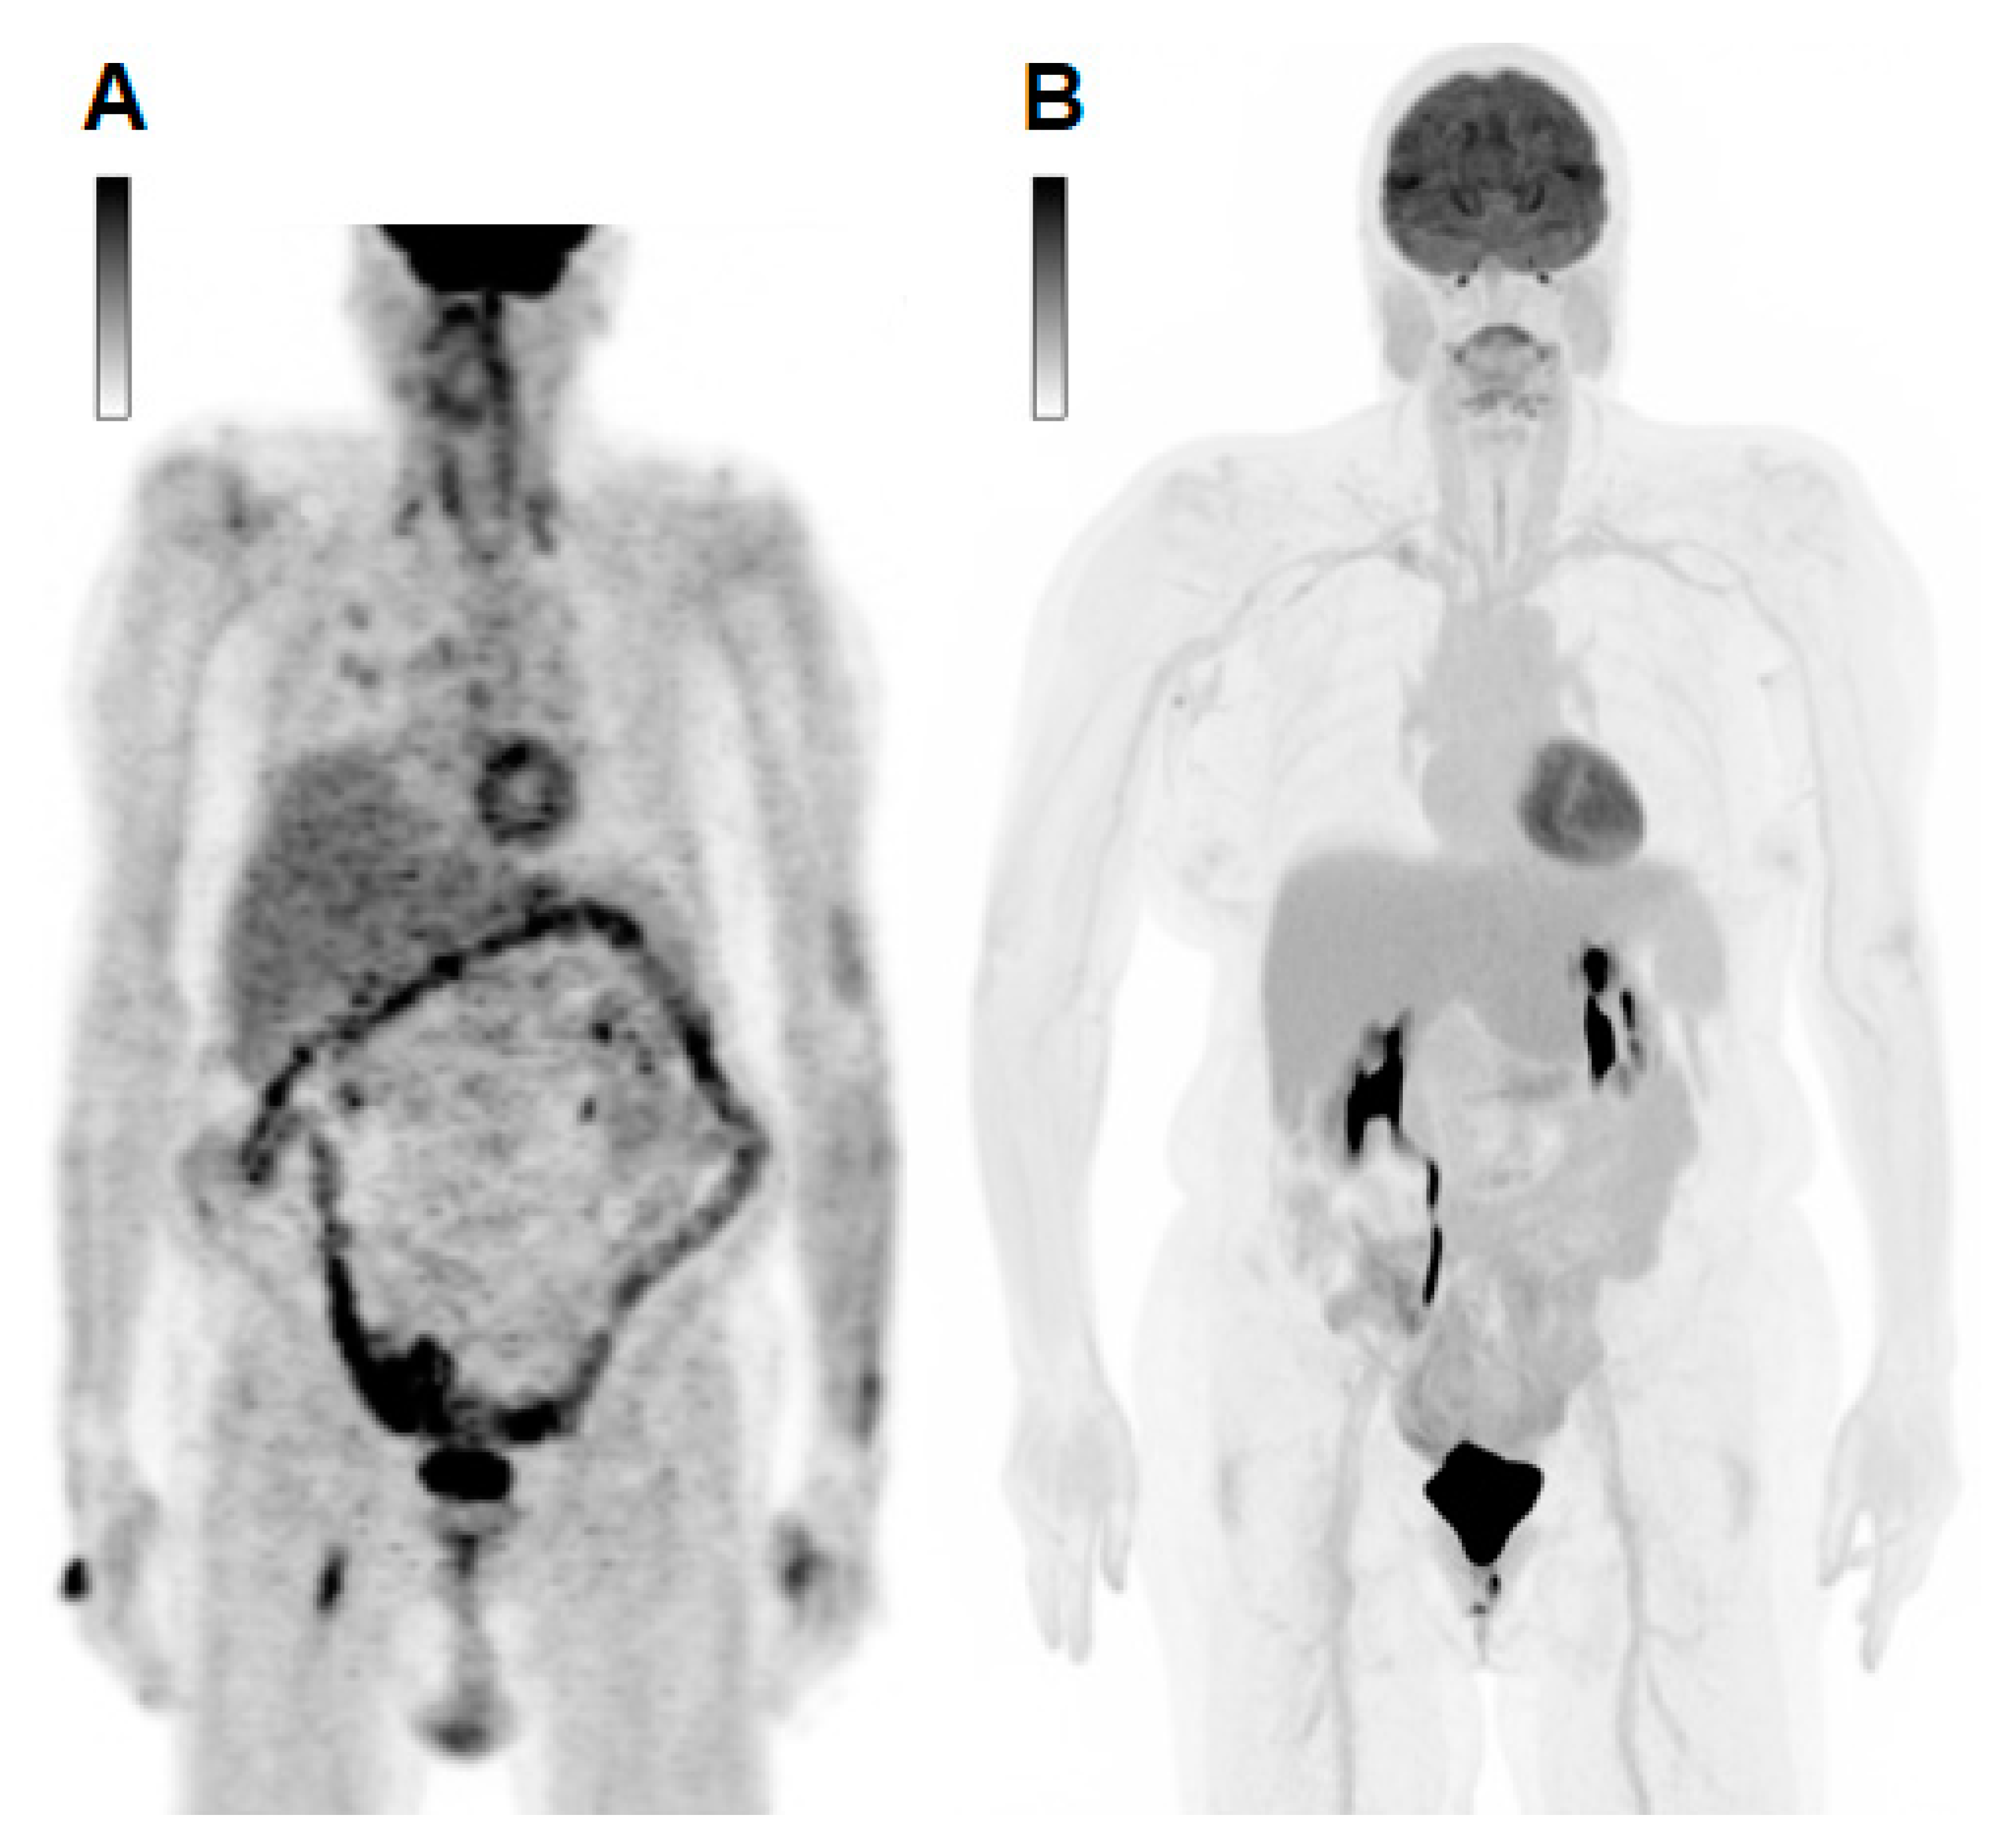

3.1. Assessment of Disease Extent and Quantitative Global Disease Assessment

- higher scanner sensitivity and consequently improved image quality, demonstrating sites of uptake previously unseen on conventional PET that may result in earlier detection of tumor lesions;